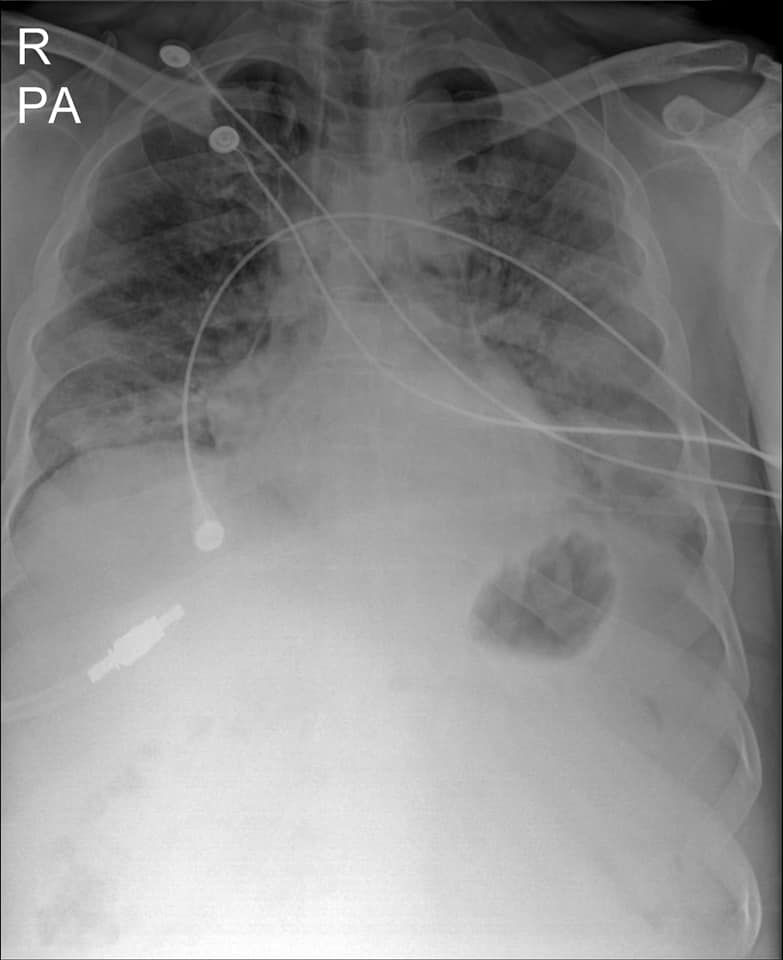

“មានបទពិសោធន៍ជាង1ឆ្នាំក្នុងគ្រប់គ្រង និងព្យាបាលជំងឺកូវីដដោយគ្មានការភ័យខ្លាចឬតក់ស្លុតឡើយ ។ តែក្នុង1ខែចុងក្រោយនេះចាប់ពី 20 កុម្ភៈ 2021 ខ្ញុំមានអារម្មណ៍ភ័យខ្លាច និងព្រួយបារម្ភណាស់ ពីព្រោះវាជាប្រភេទមេរោគប្រែរូបថ្មី (variant virus strain) ដែលក្នុងរយៈពេលតែ2ទៅ5ថ្ងៃវាវាយលុកចូលសួតធ្វើអោយរលាកធ្ងន់ធ្ងរទាំងសងខាង ។ រូបភាពសួតត្រូវបានមេរោគស៊ីសុះសាច់ដ៏គួអោយខ្លាច ។